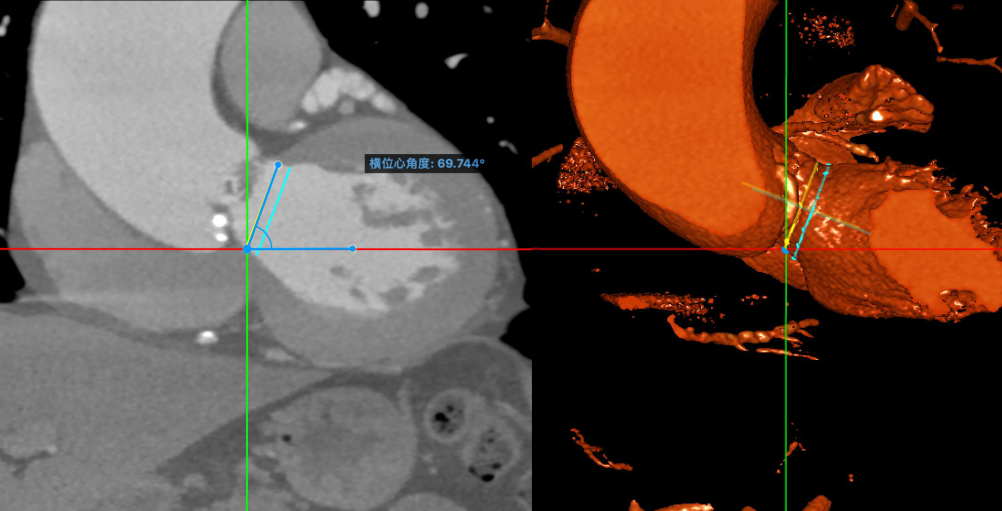

横位心角度:70度

钙化情况:3D重建

术前心血管内科、心胸外科、超声科、麻醉科、体外循环、介入室等科室进行了术前讨论和术前策略分析:该患者为二叶式主动脉瓣,Type 0型。瓣叶重度钙化,钙化主要分布瓣叶、瓣叶交界。考虑患者主动脉瓣膜二叶式畸形,钙化严重,而且横位心角度较大(70度)。